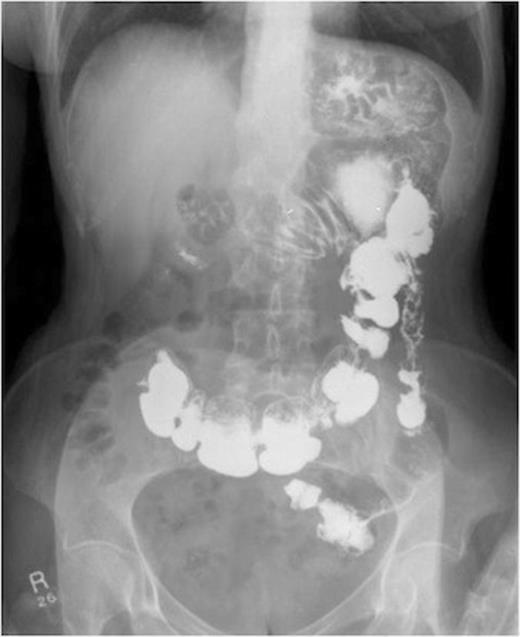

She then had a barium meal and follow through which clearly demonstrated a gastro-colic fistula. This was confirmed by colonoscopy which demonstrated the fistula. There were no signs of neoplasia and the no malignancy was witnessed on biopsy. These findings were confirmed on CT.

A series of radiographs from barium swallow demonstrating gastro-colic fistula